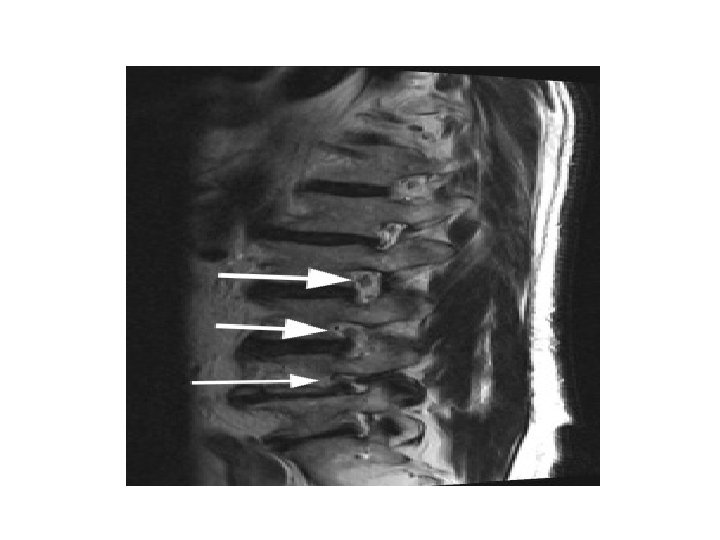

• Pathophysiology : Compression can lead to either foraminal stenosis mainly , lateral recess stenosis or rarely central stenosis. § foraminal stenosis : mainly : – Adult isthmic spondylolisthesis at L 5/S 1 often leads to radicular symptoms caused by compression of the exiting L 5 nerve root in the L 5 -S 1 foramen. compression can be caused by : • hypertrophic fibrous repair tissue of the pars defect • uncinate spur formation of the posterior L 5 body • bulging of the L 5/S 1 disc § lateral recess stenosis • caused by facet arthrosis mainly or hypertrophic ligamentum flavum. § central stenosis • rare due to fact that these slips are usually only Grade I or II

- neurologic symptoms caused mainly by central and lateral recess stenosis and to a less degree foraminal stenosis. § Central and lateral recess stenosis : • degenerative slip at L 4/5 will affect the descending L 5 nerve root in the lateral recess. - caused by slippage, hypertrophy of ligamentum flavum, and encroachment into the spinal canal of osteophytes from facet arthrosis.

• Imaging : - X-ray : AP , lateral , oblique * on lateral view : forward slip is evident. * on oblique view : gap in pars interarticularis. - MRI : to evaluate impingement of neural elements. - CT : for bony pathology. - CT myelogram : when MRI contraindicated.